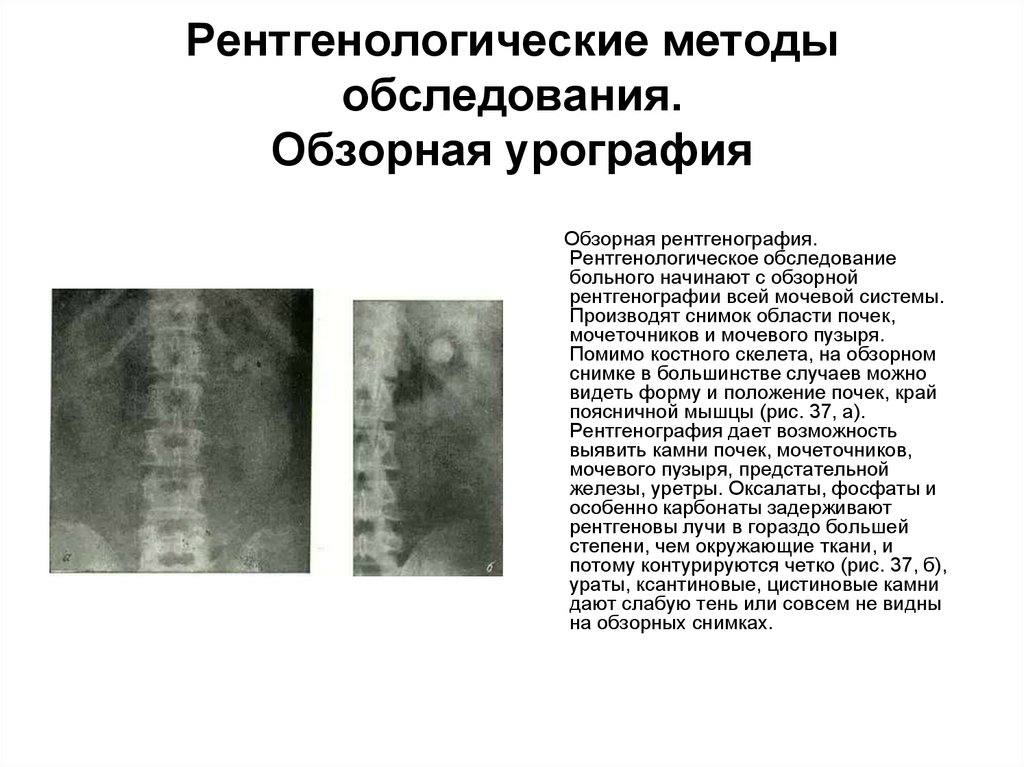

Медицинские изображения: Обзорная рентгенография урография

Раздел: Фокус на знании